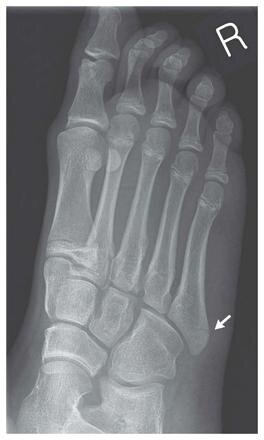

14歳の少女はバランスWiiボードで足の骨を折ってしまったそうです。

The New England Journal of Medicine is owned, published, and copyrighted (C) 2010 Massachusetts Medical Society. All rights reserved.

14歳の少女がバランスWiiボードで足を折る-「従来のゲーム機より怪我する率が高く見える」